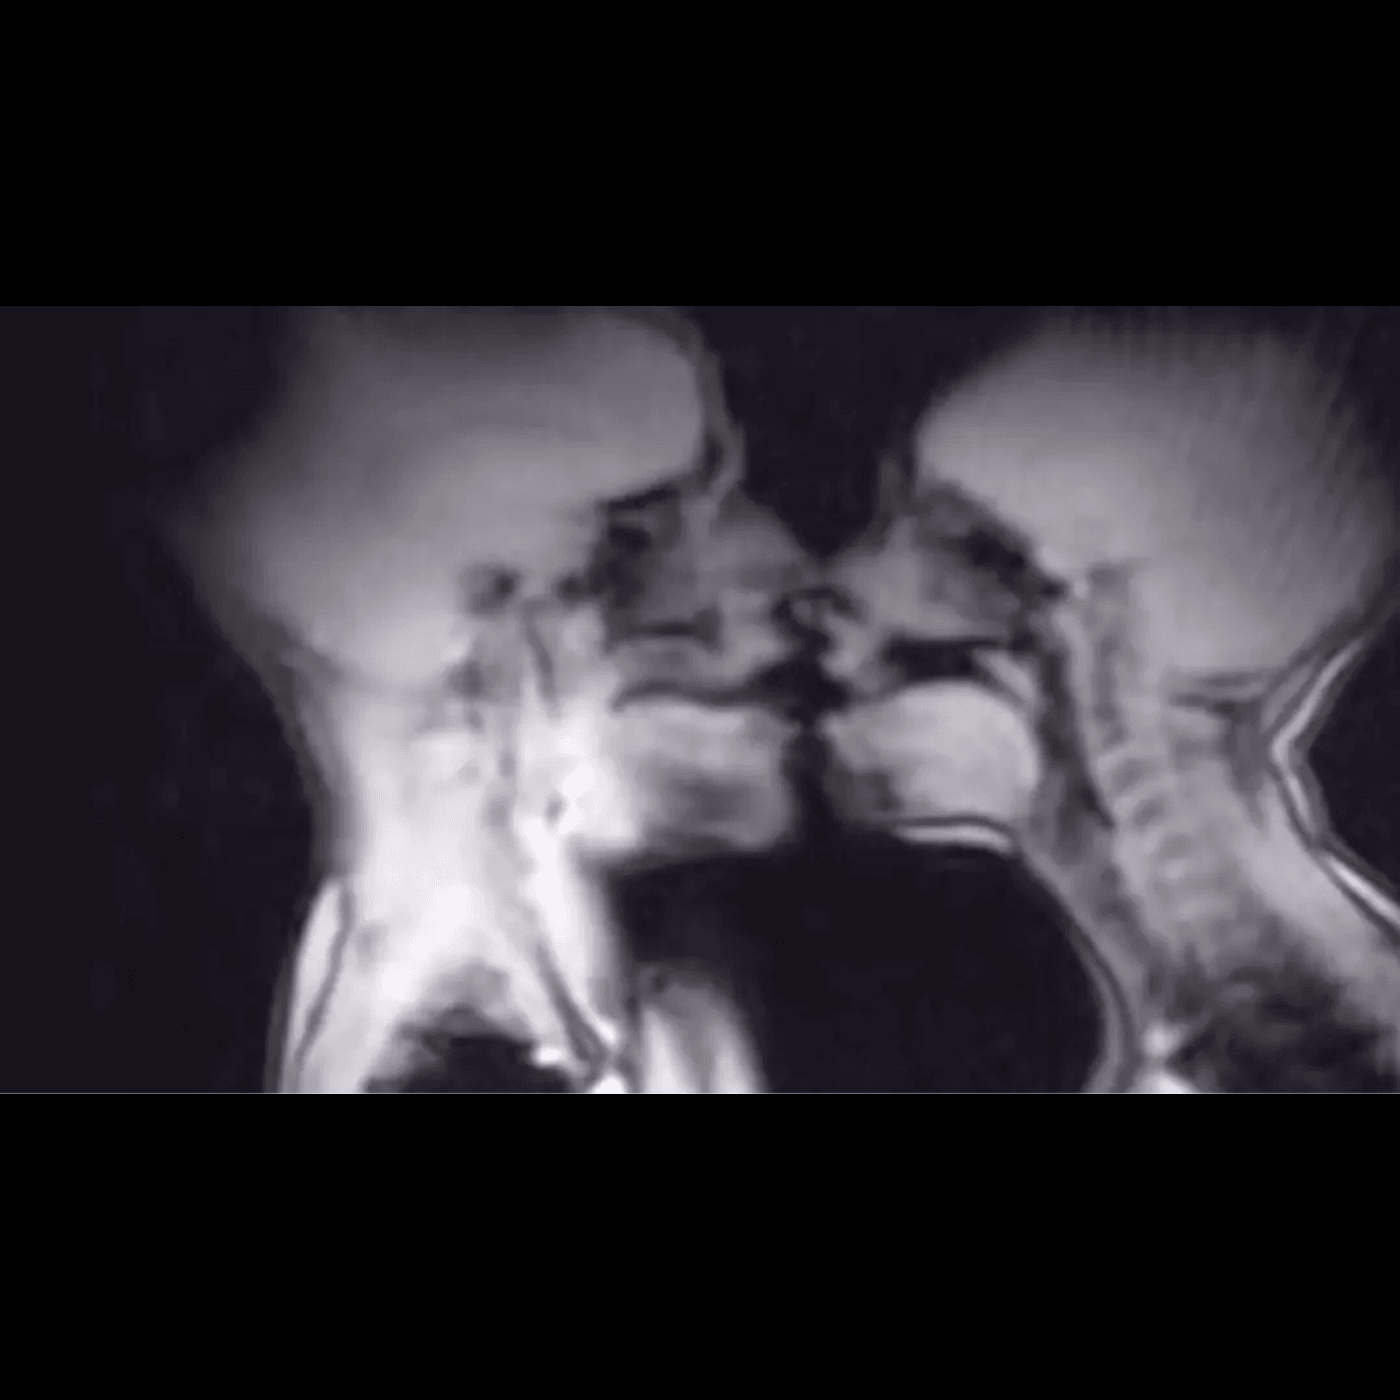

În 1991, Ida Sabelis și partenerul ei, Jupp, au avut un act sexual într-un aparat de imagistică prin rezonanță magnetică (RMN) pentru un experiment științific revoluționar. Rezultatele au oferit primele imagini detaliate ale corpului uman în timpul actului sexual și au adus contribuții importante în studiul anatomiei.

Conform studiului publicat în British Medical Journal în 1999, cercetătorii au concluzionat că „realizarea imaginilor prin rezonanță magnetică a organelor genitale masculine și feminine în timpul coitusului este fezabilă și contribuie la înțelegerea anatomiei”.

Rezultatele au fost surprinzătoare. Studiul a arătat că, în timpul actului sexual în poziția „misionarului”, penisul are forma unui bumerang, iar o treime din lungimea sa constă din rădăcina penisului. În ceea ce privește femeile, în timpul excitării sexuale fără contact sexual, uterul se ridica, iar peretele vaginal anterior se lungea. Dimensiunea uterului nu creștea însă pe durata excitării sexuale.